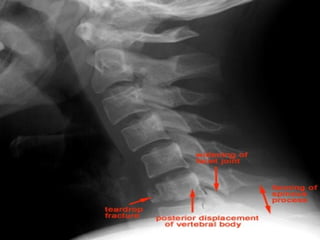

FLEXION TEARDROP FRACTURE

 Posterior ligament disruption and anterior compression fracture

of the vertebral body which results from a severe flexion injury

 Mechanism: hyperflexion and compression (e.g. diving into

shallow water)

 Best seen on lateral view

 Signs:

 Prevertebral swelling associated with anterior longitudinal

ligament tear

 Teardrop fragment from anterior vertebral body avulsion

fracture

 Posterior vertebral body subluxation into the spinal canal

 Fracture of the spinous process

 unstable

FLEXION TEARDROP FRACTURE Posterior ligament disruption and anterior compression fracture of the vertebral body which results from a severe flexion injury  Mechanism: hyperflexion and compression (e.g. diving into shallow water)  Best seen on lateral view  Signs:  Prevertebral swelling associated with anterior longitudinal ligament tear  Teardrop fragment from anterior vertebral body avulsion fracture  Posterior vertebral body subluxation into the spinal canal  Fracture of the spinous process  unstable